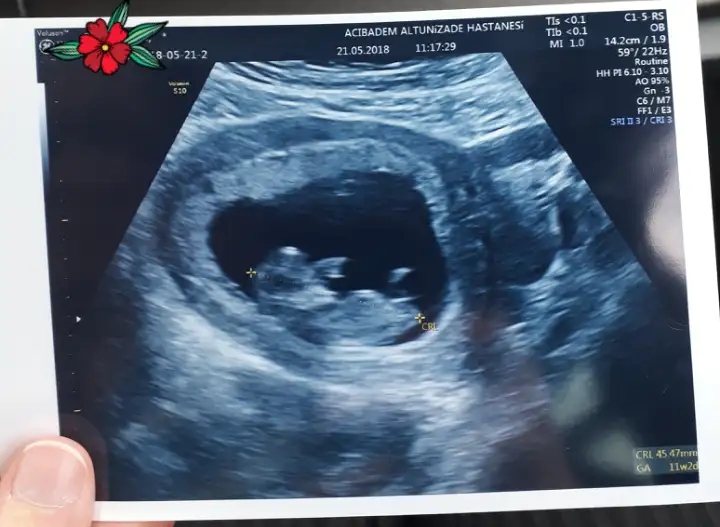

Balım ilk gonderdigin foto da nub belli degil ama ikinci gonderdigin fotodaki gördüğüm nubsa eğer,kız senin bebisin:))) kızın olcaaaaaakkkk :emir_bebek::KK71:

Son gittiğimizden bir fotoğraf daha var. Onu da yükleyeyim, bir bak bakalım. Son gittiğimizde doktor bir fikrim var aslında ama %70 ihtimal dedi, o yüzden bize söylemedi :KK48:

Nub çıkıntısi cinsiyetin tam yerlesmeden bi onceki adımı gibi birsey kuzu :)))) yani o çıkıntı zamanla iceri giriyor ve cinsiyeti olusturuyor.nub cizgisi dik gidiyorsa erkek paralel gidiyorsa kiz oluyor. LezzetliCipetpet LezzetliCipetpet in kesin kız mesela gördüğüm nubsa. Emira SY Emira SY inki bariz erkek :D

Nub çıkıntısi cinsiyetin tam yerlesmeden bi onceki adımı gibi birsey kuzu :)))) yani o çıkıntı zamanla iceri giriyor ve cinsiyeti olusturuyor.nub cizgisi dik gidiyorsa erkek paralel gidiyorsa kiz oluyor. LezzetliCipetpet LezzetliCipetpet in kesin kız mesela gördüğüm nubsa. Emira SY Emira SY inki bariz erkek :KK70:

Bende hic anlamazdim nub tan fistigim.doktorda net anlayamamisti.ben internetten arastira arastira baka baka kendi kızımı nub undan ogrendim.yani doktor soylemeden ben ogrenmistim kızım olacagini :D doktor 1 ay sonra net soyledi